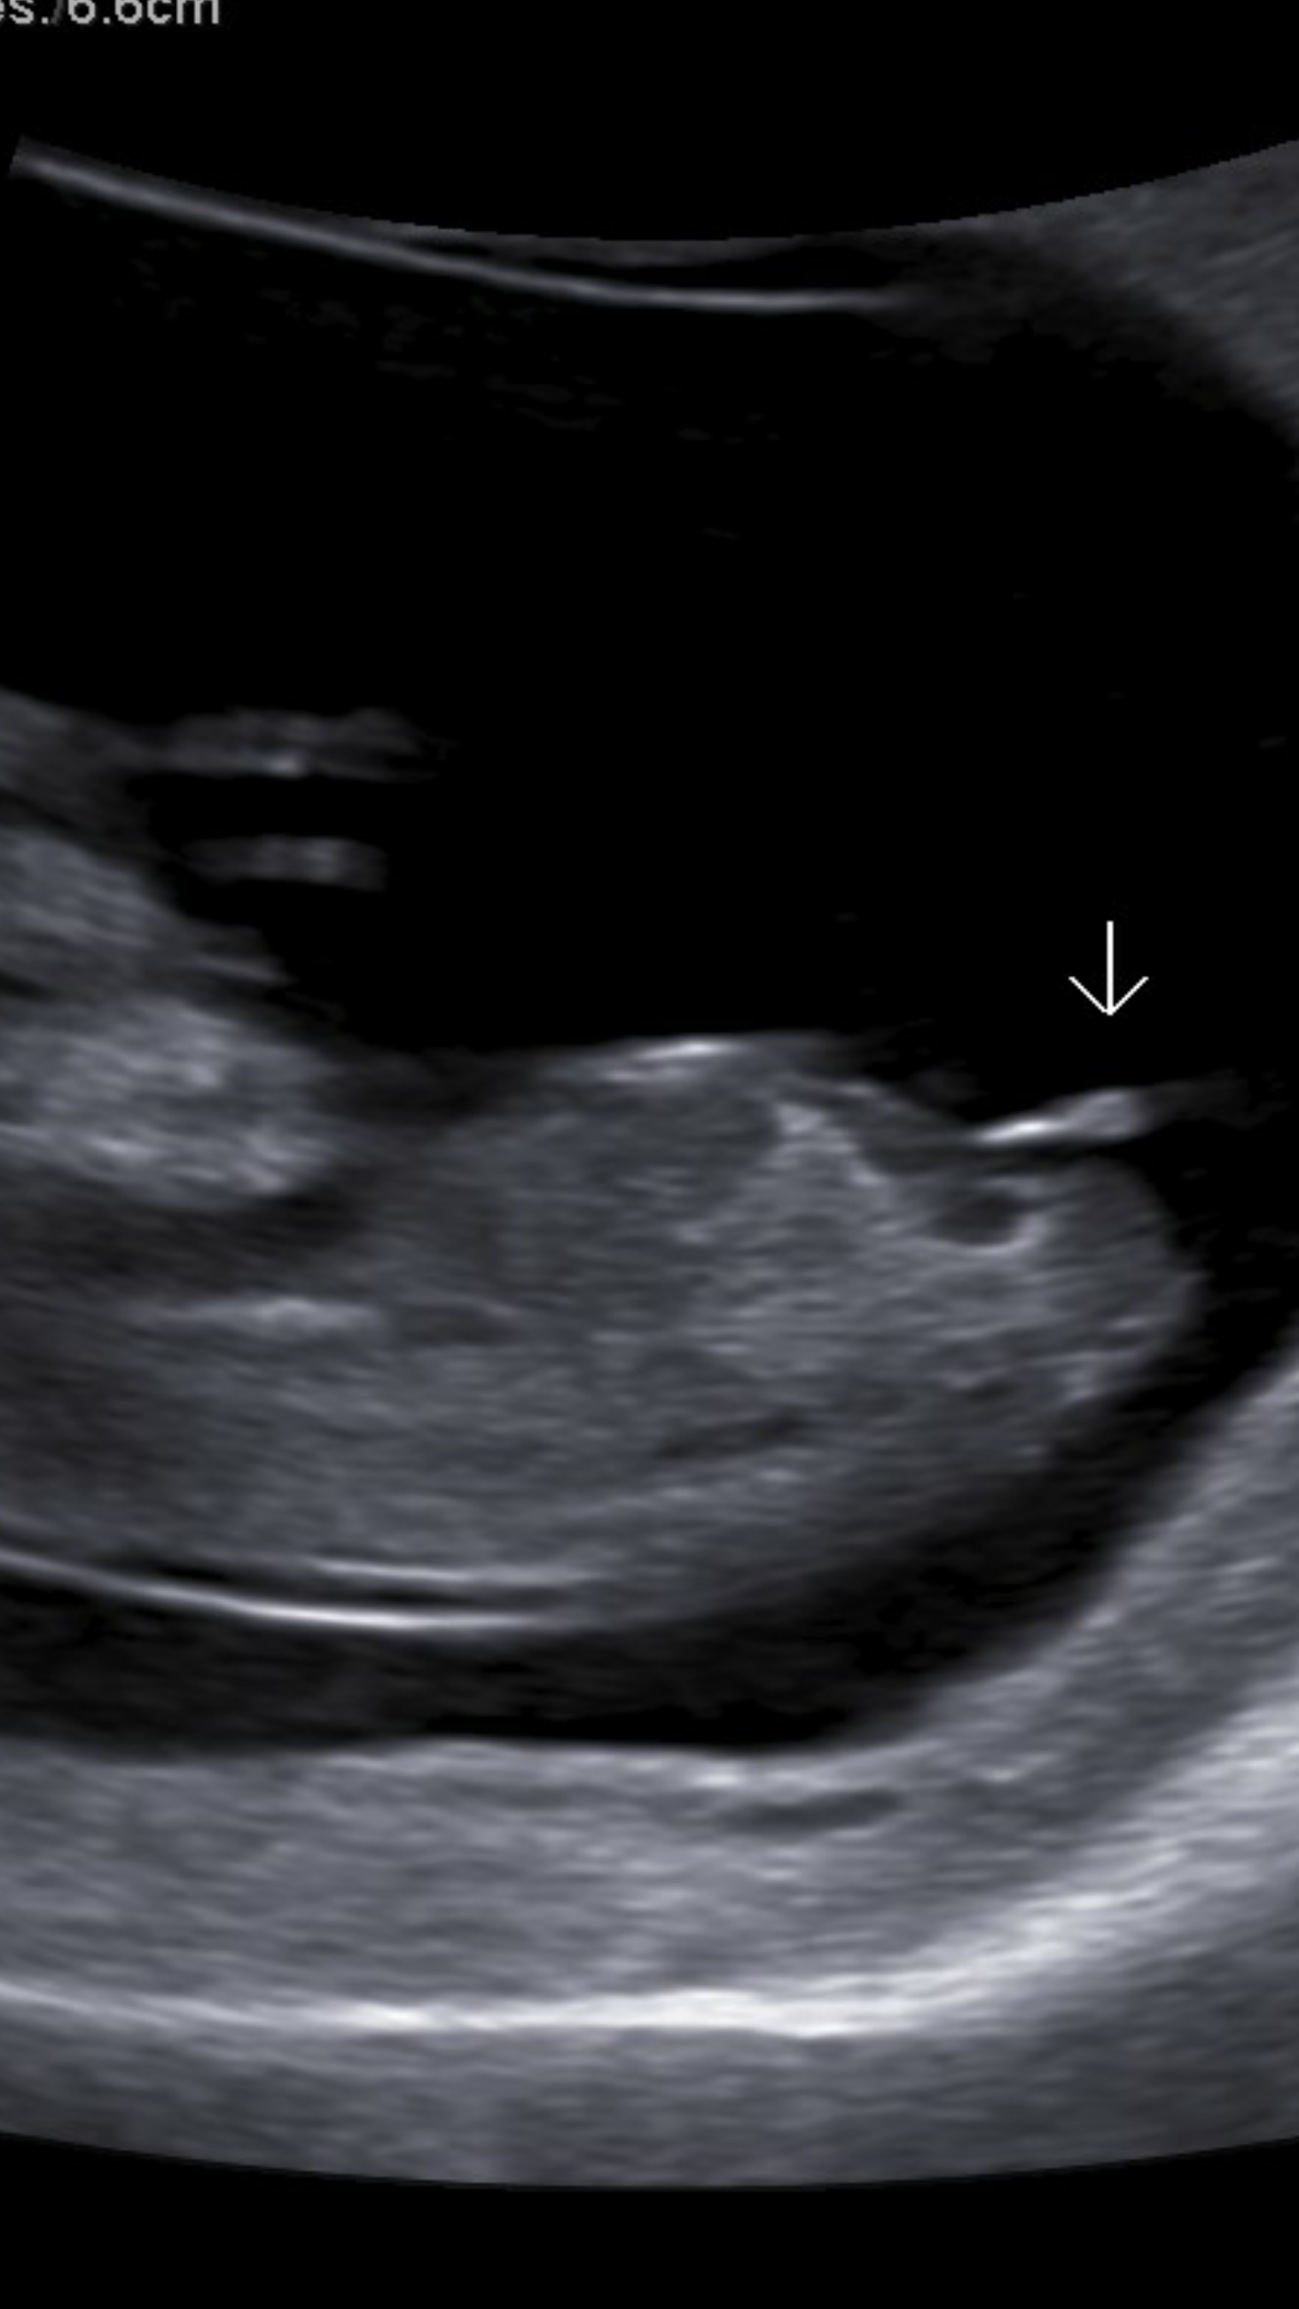

hi ladies got this ultrasound done at 12 weeks 2 days and the tech said the nub looked very much like a girl. We're really hoping so what do you think?